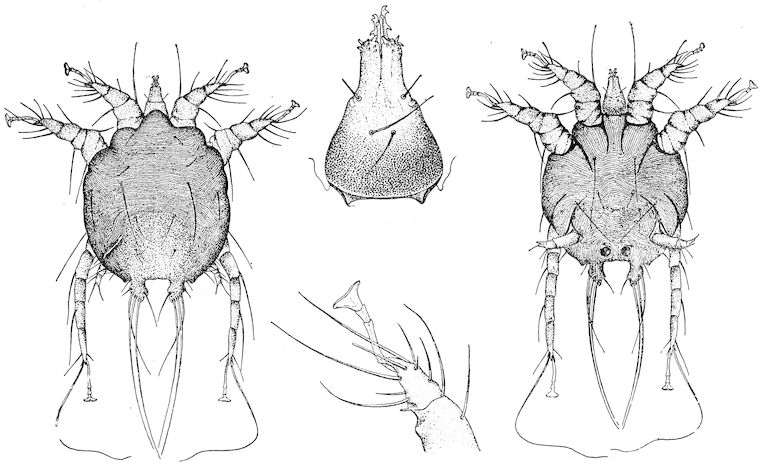

| Scabies—Scab—Mange | 611 | |||

| Scabies in sheep | 611 | |||

| Sarcoptic scabies | 612 | |||

| Psoroptic mange—Sheep scab | 614 | |||

| Chorioptic mange—Symbiotic mange—Foot scab | 636 | |||